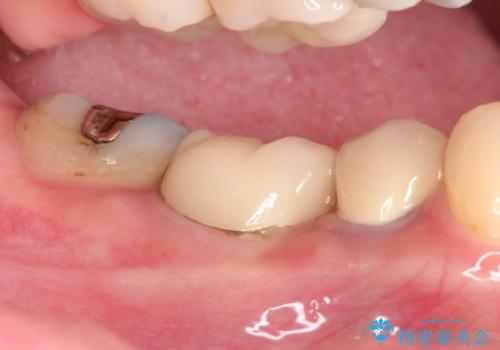

【外部吸収】根管治療、外科治療からのオールセラミッククラウン

- 歯肉の腫脹と被せ物の不適合を主訴に来院されました。

根管治療後、外部吸収を認めたため歯周外科を行ない歯冠修復を行なっております。

根管治療後には速やかに歯冠修復が必要です。